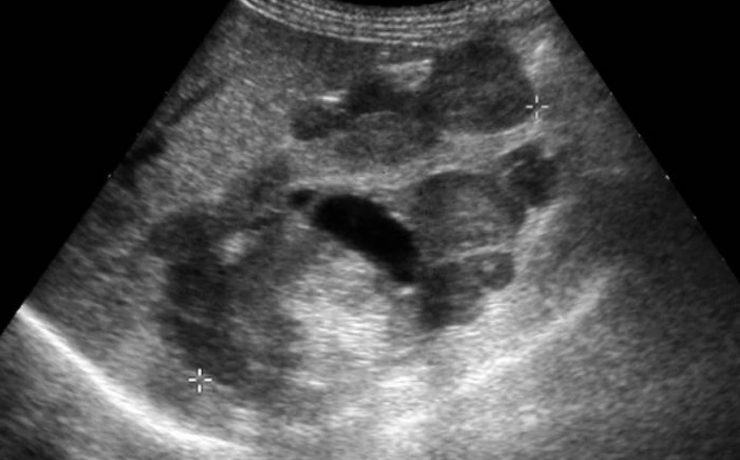

Existen alteraciones ováricas valorables por ecografía tratándose generalmente de alteraciones foliculares las cuales se presentan clínicamente como defectos en la maduración además del número de los mismos. Ecográficamente se diferencia el tamaño, el grosor capsular y su estroma puede estar aumentado e hiperecogénico. Otra patología son los quistes que